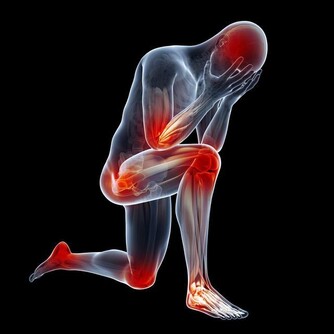

腳雖然位於人體最低處,但它是身體健康的“指向標”之一,所以才有“百病始於腳,養生先養腳”的說法。

而很多人不知道的是,腳上有很多經絡通向肝臟,通過觀察腳上的變化就能判斷肝臟的健康狀況。

腳上出現這4個信號,說明你的肝越來越差!

正常健康腳掌顏色應是白裡透紅,如果腳掌發白,無血色,可能是血液垃圾過多,致使血管淤堵,供給腳掌的血液不夠,腳掌自然呈現出發白的症狀,出現這種情況且伴有頭暈、眼花、無力等症狀時,應留意肝臟健康。

中醫學認為,正常腳底顏色略紅。排除一些角質層較厚的人會出現腳底發黃之外,還可能與肝臟有關係,當肝細胞破壞,使得血中的膽紅素不能正常的排除,逆流至血液中,呈現出腳底發黃。

3、腳底乾燥

很多人認為,腳底乾燥是因為腳部皮膚疾病而導致的,殊不知腳底肌膚與身體內分泌有關,當肝細胞受損時,可能影響身體內分泌正常,進而導致皮膚暗黃、腳底變得乾燥,常出現脫皮、乾裂情況,這些情況應留意是否是肝臟受損。

4、腳掌紋路增多

中醫認為,肝主藏血,肝臟每天會分解血液中的毒素或代謝產物,當肝臟受損時,其解毒能力也會有所下降,血液健康也可能受到一定影響。腳距離心臟較遠,如果腳掌紋路增多且變得明顯,要注意腳下保暖和保養肝髒了。

另外,女性們腳趾腹側面如果出現很深的粗紋,或者有針孔狀,需警惕婦科問題,例如內分泌失調、月經失調等。